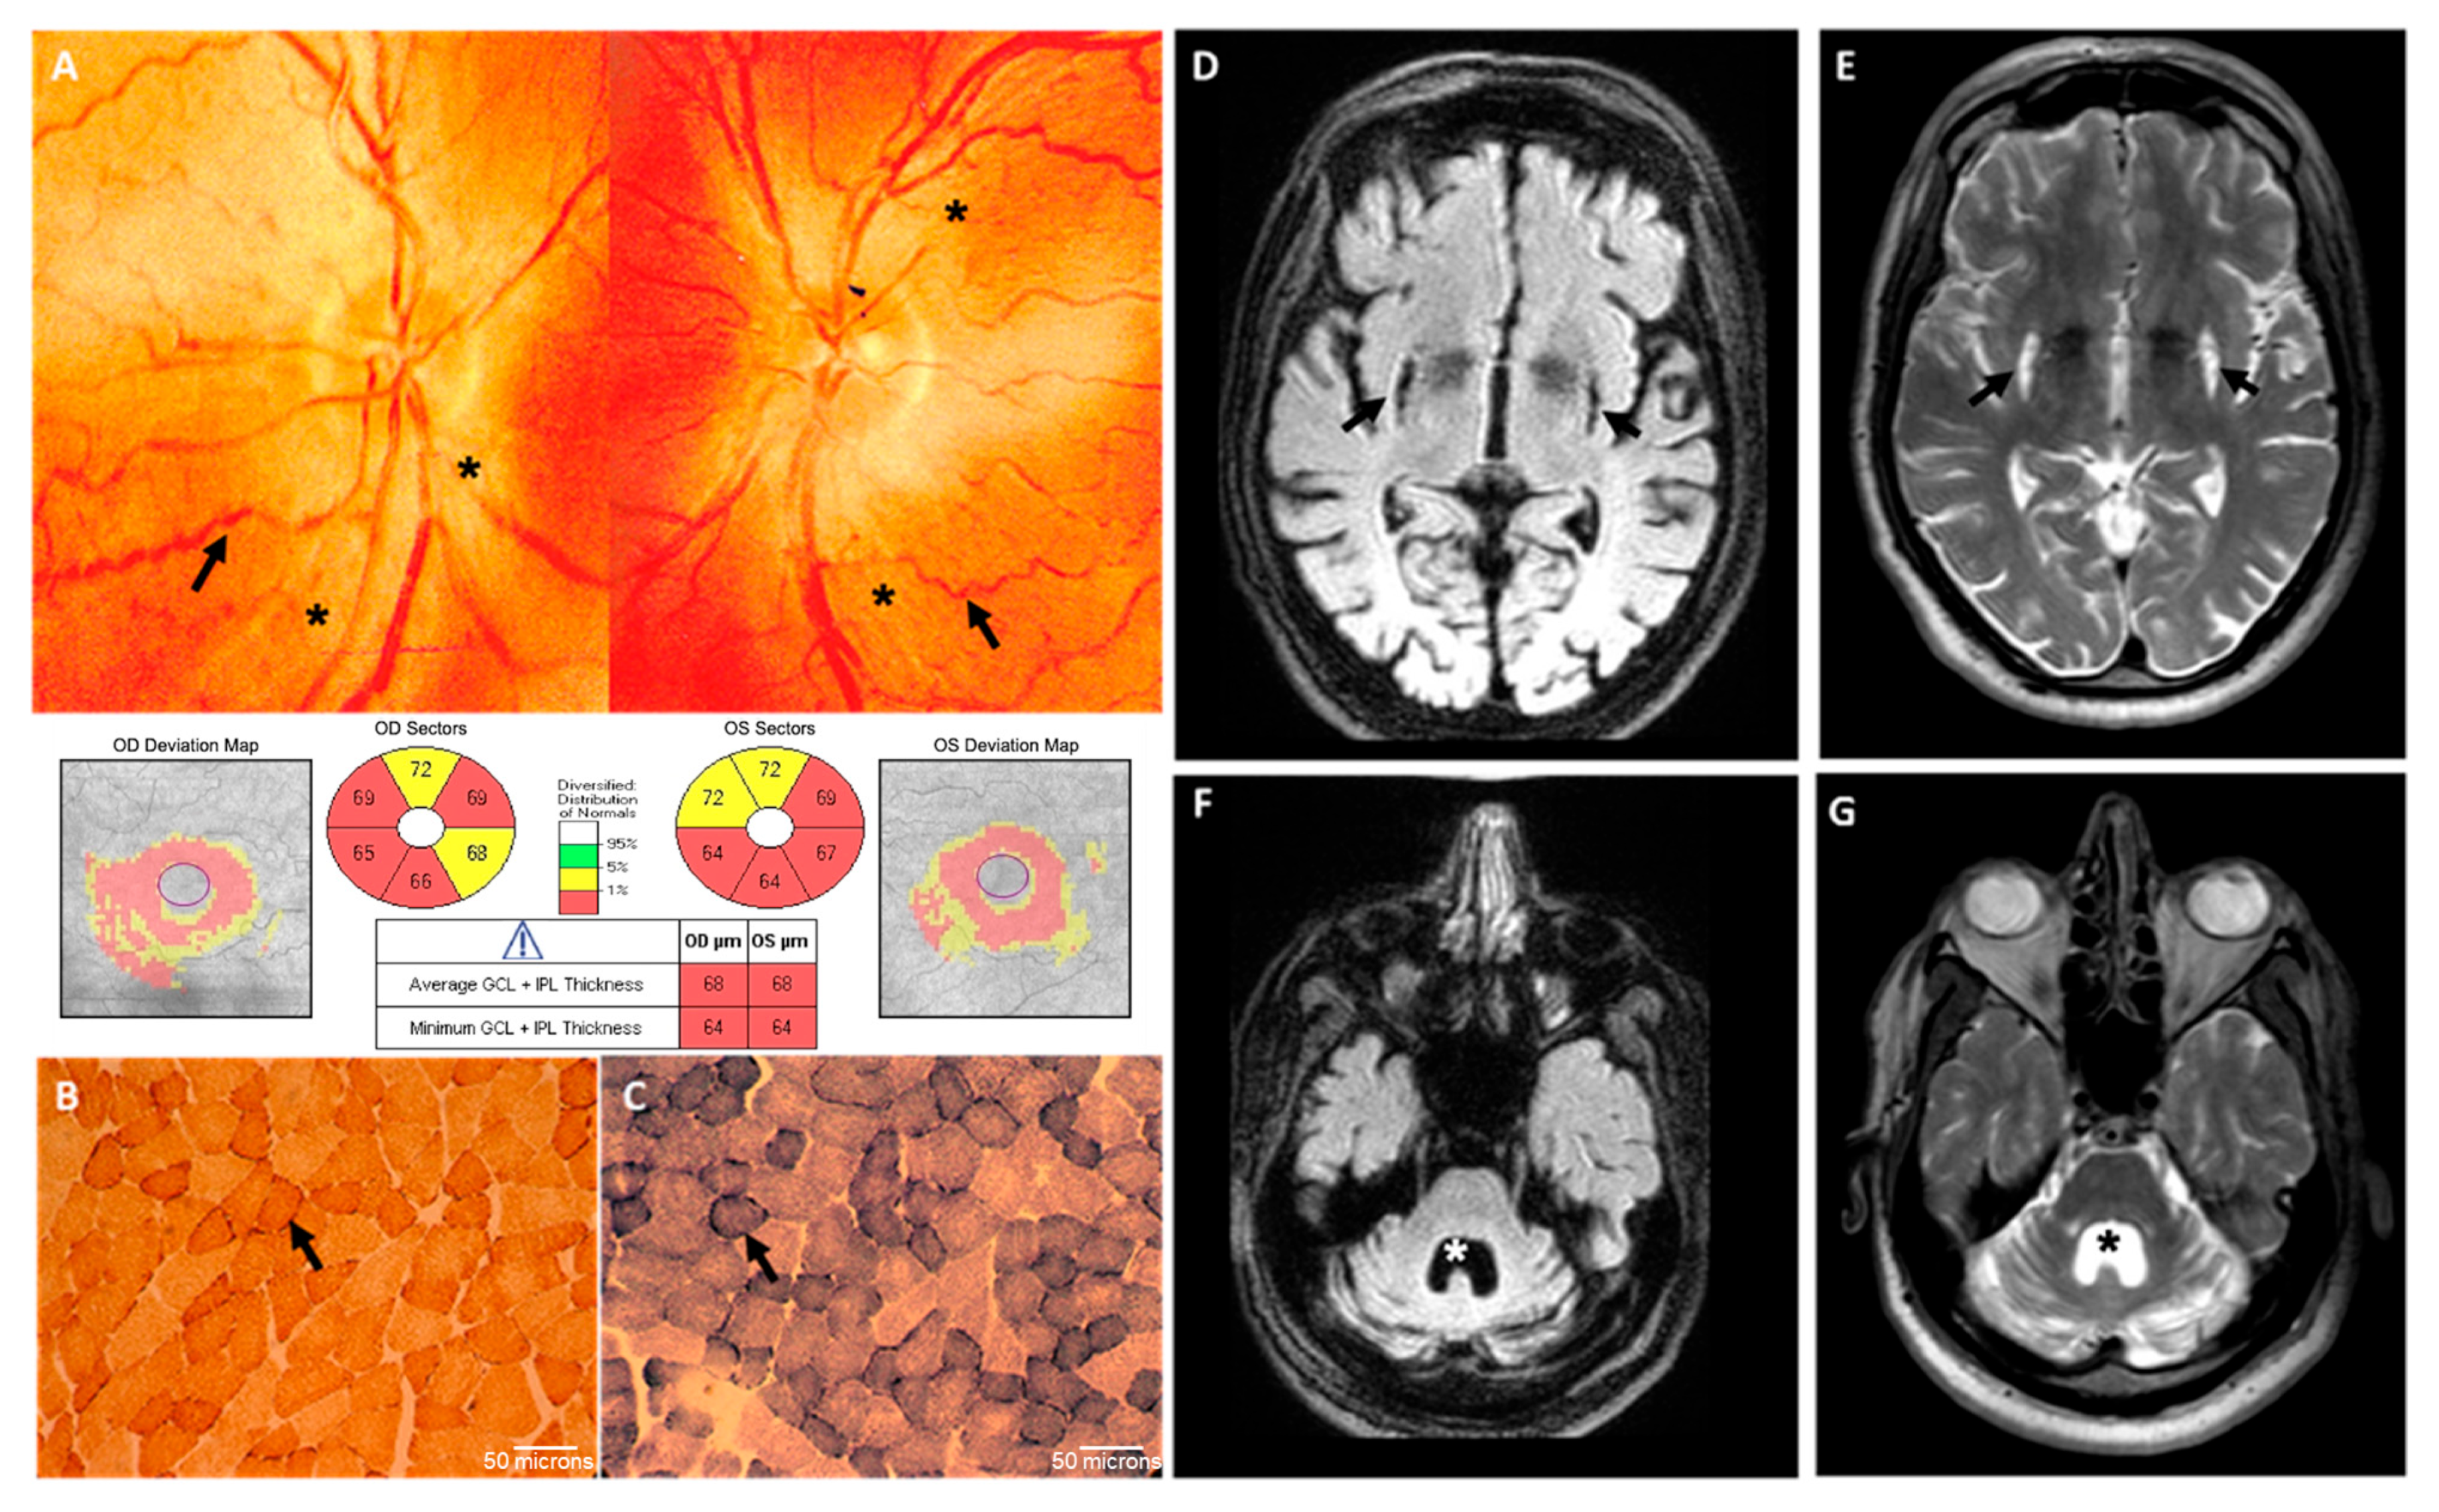

Brain CT scan showed symmetric bilateral basal ganglia lesions and mild cerebellar atrophy. EMG was normal, while EEG showed sporadic theta activity. Laboratory exams were normal except for a mild increase in lactic acid levels after standardized exercise (25.3 mg/dL; nv 5–22 mg/dL), which did not promptly recover after 15 min of resting (23 mg/dL). At 16 years of age, he started complaining of dysphagia, and bilateral sensorineural hearing loss was recognized at audiometry. At 23 years, he also showed progressive visual loss. Neuro-ophthalmologic examination showed moderate swelling of the retinal fibers at the optic nerve head and some tortuosity of the peripapillary vessels on fundus picture, whereas optical coherence tomography (OCT) documented loss of retinal ganglion cells in the macula (Figure 2A). Photopic and scotopic ERG showed abnormal bilateral responses. Muscle biopsy performed at 23 years of age showed only some subsarcolemmal increase in cytochrome c oxidase (COX) and succinate dehydrogenase (SDH) staining, indicative of moderate proliferation of the mitochondrial mass (Figure 2B,C). Electromyography was normal.

Brain MRI confirmed the presence of bilateral striatal necrosis and severe cerebellar and mild brainstem atrophy (Figure 2D–G). DaT-SCAN imaging showed normal pre-synaptic uptake of the dopamine transporter tracer at the level of the caudate and proximal putamen, whereas this uptake was absent at the level of the medium–distal putamen bilaterally. Cardiological evaluation showed left ventricular non-obstructive hypertrophy and right bundle conduction defect.

Figure 2. Clinical data of the proband: (A) Optical coherence tomography (OCT). The fundus photography images of the patient’s eyes display a moderate swelling of the optic disc fibers (asterisks) without cup and the presence of peripapillary microangiopathy (arrows) (top panel); structural OCT performed in the macular area confirmed a thinning of the GC-IPL in the central area around the fovea (bottom panel); GC-IPL: ganglion cell inner plexiform layers. (B,C) Muscle biopsy from the proband: histoenzymatic staining for both COX and SDH activities revealed increased subsarcolemmal staining (arrows), indicative of a moderate increase in mitochondrial mass, which is usually a compensatory feature. No COX-deficient or ragged red fibers were observed. (DG) Brain MRI: bilateral striatal necrosis (arrows) (D,E), severe cerebellar atrophy and mild brainstem atrophy with consensual 4th ventricle dilation are evident (asterisk) (F,G).